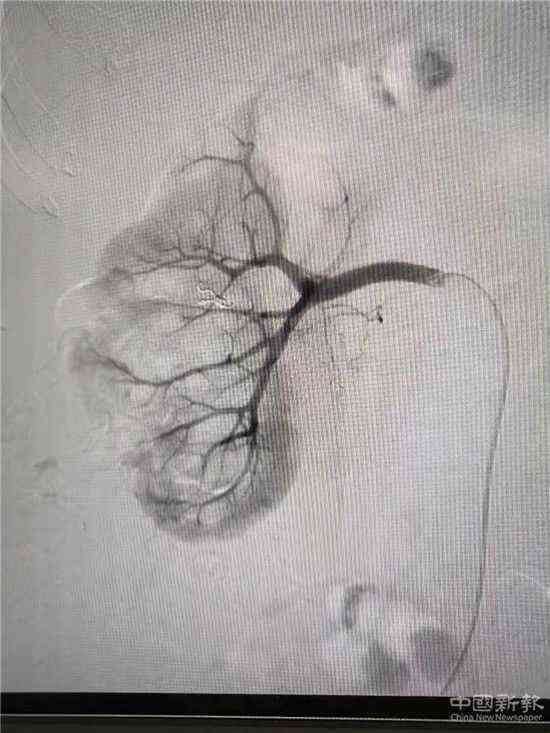

栓塞后造影圖(已止血)

家住湖南省郴州市嘉禾縣廣發(fā)鎮(zhèn)的鄧大媽,因患巨大腎結(jié)石進(jìn)行了“經(jīng)皮腎鏡取石術(shù)”,術(shù)后第3天出現(xiàn)大量鮮紅色血尿。經(jīng)過(guò)增強(qiáng)CT檢查,考慮為“腎穿刺口處動(dòng)脈出血”,醫(yī)院介入血管外科團(tuán)隊(duì)立即為患者在DSA下行“微創(chuàng)介入右腎出血?jiǎng)用}栓塞術(shù)”,術(shù)后出血立刻停止,尿液由紅色轉(zhuǎn)為正常顏色。